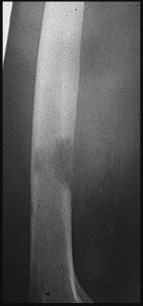

Question 3:

Mutations in the IDH1 and IDH2 genes are heavily implicated in the pathogenesis of cartilaginous tumors. Somatic mosaic mutations in these genes are found in over 80% of patients with Ollier disease and Maffucci syndrome, both of which are forms of enchondromatosis. Multiple Hereditary Exostoses is associated with EXT1/EXT2 mutations. McCune-Albright is associated with GNAS mutations. NF1 is associated with the neurofibromin gene.